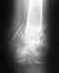

Рентгенограмма переломов голени ч/з 34 дня после операции.

Прошу прокомментировать рентгенограмму.

Переломы закрытые, рентгенограмма через 34 дня после интрамедуллярного остеосинтеза стержнем Chm с компрессией.Скан: http://s40.radikal.ru/i089/0902/56/f896d3cdf81b.jpgИнтересует, указанное зелеными стрелками - костная мозоль или нет? И что вообще можно сказать о ходе срастания и о разрешении начинать нагрузку ноги.В период 25 дней с операции принимал "Кальций Д3" и мумие 0,5гр/сутки.

Указаны области переломов. Что-то там уже появляется. Все сделано хорошо, не оснований ожидать проблем.

Снимков верхнего конца стержня нет. Видимо, синтез компрессионно-динамический, т.е. нагрузка передается через зону перелома. Ее можно дозировать по хромоте. Избыточную нагрузку переносить на костыли или трость в противоположной руке. То есть опираться на ногу так, чтобы не хромать. Но важнее пораньше разработать движения в голеностопном суставе. Особенно стопу на себя чтобы можно было потянуть на тот же угол, что на здоровой ноге. Сесть на корточки.